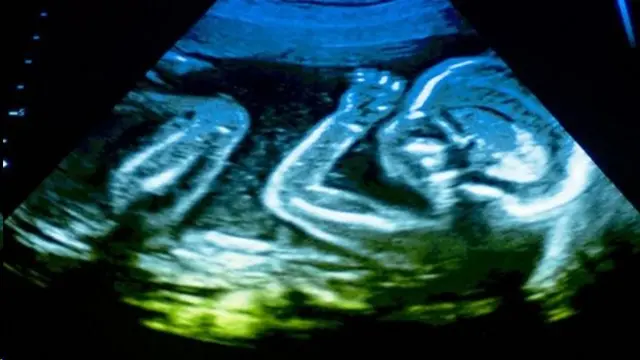

Сүрөттүн булагы, Science Photo Library